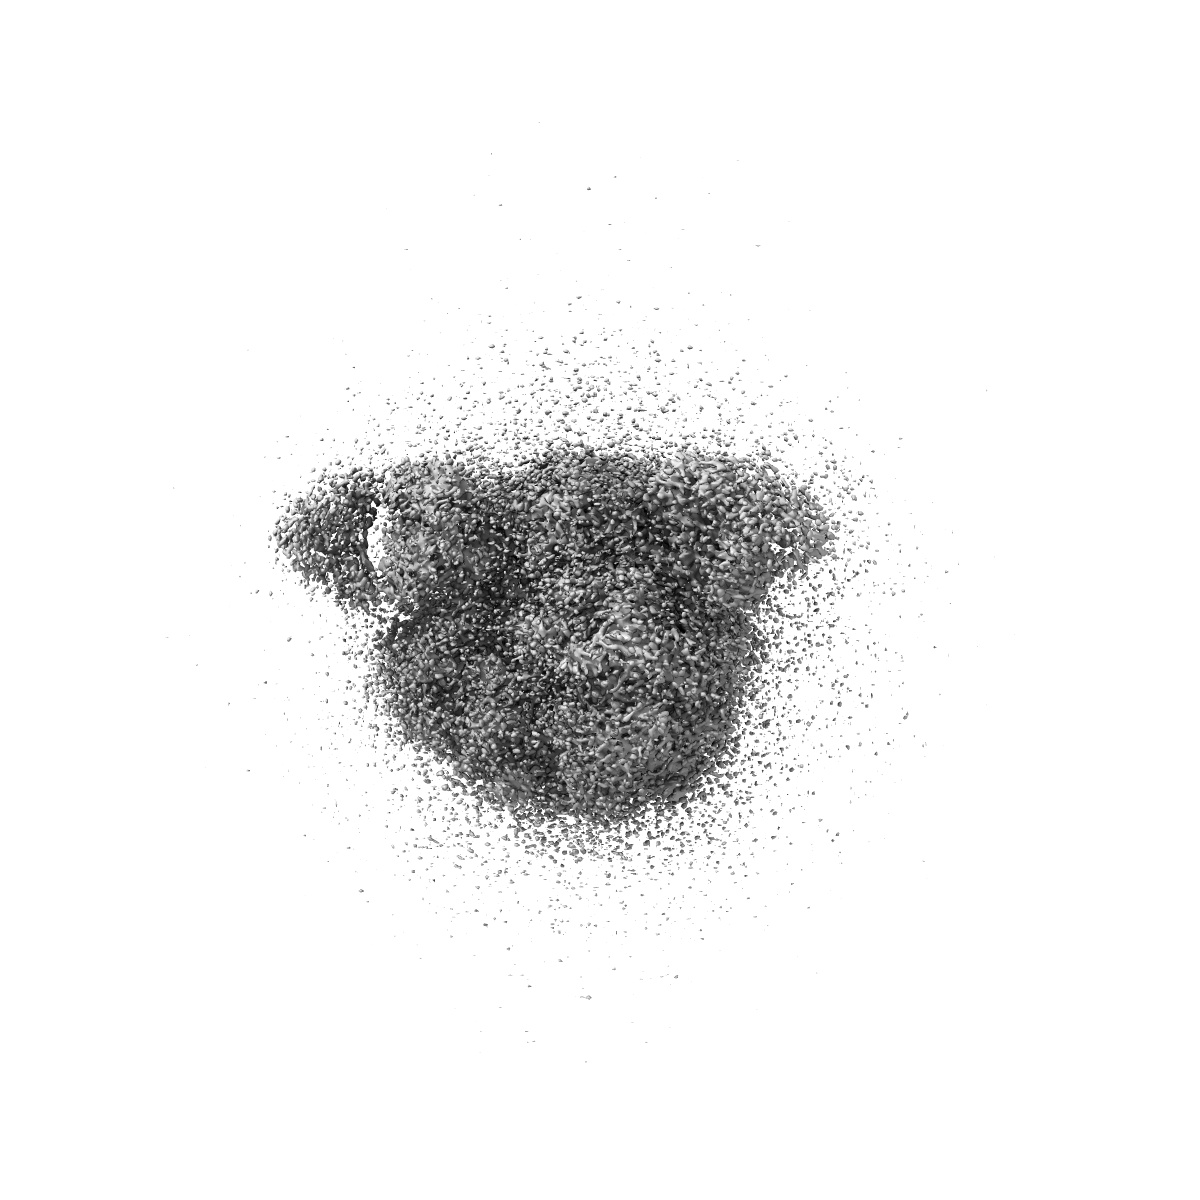

CRYO-EM STRUCTURE OF HIV-1 BG505DS-SOSIP.664 ENV TRIMER BOUND TO DJ85-b.01 FAB

Single-particle3.1 Å

Sample: BG505 DS-SOSIP DJ85-b.01 FAB COMPLEX